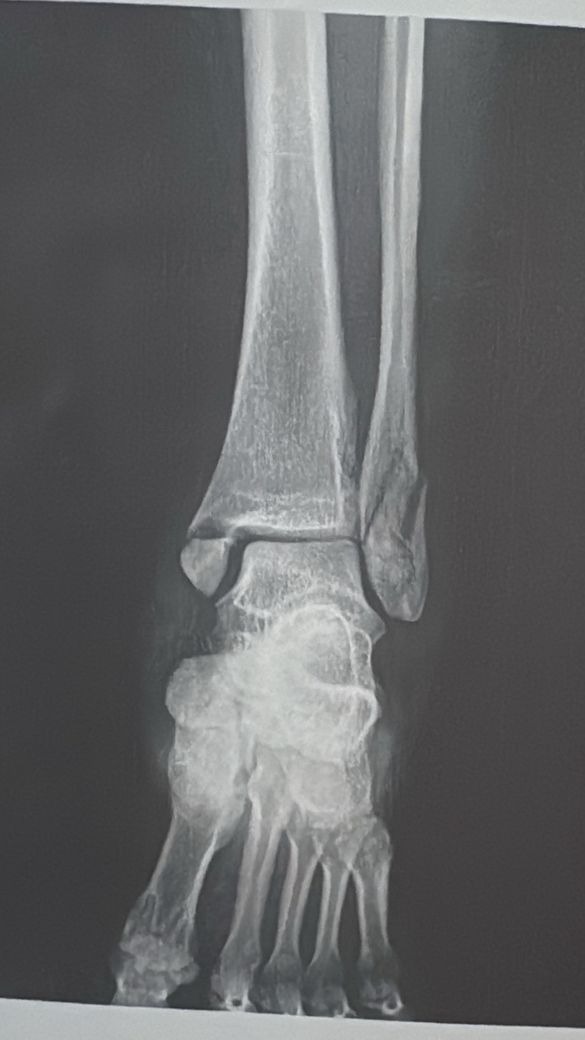

발목골절수술후 심힌 통증 및 발등 감각 둔함

발목 골절 수술을 한지 7주가 다 되어갑니다..

발목 골절수술을 하면서 연골손상 내측인데 손상 외부 근육, 힘줄 손상이 있었다고 합니다.

• 1번 째 사진